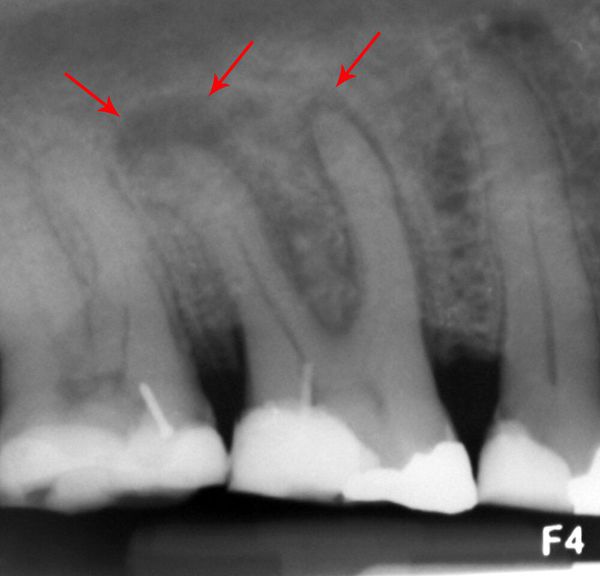

W kompleksowej diagnostyce konieczne jest wykonanie badania rentgenowskiego, które pozwala potwierdzić, że źródłem infekcji jest właśnie ząb.